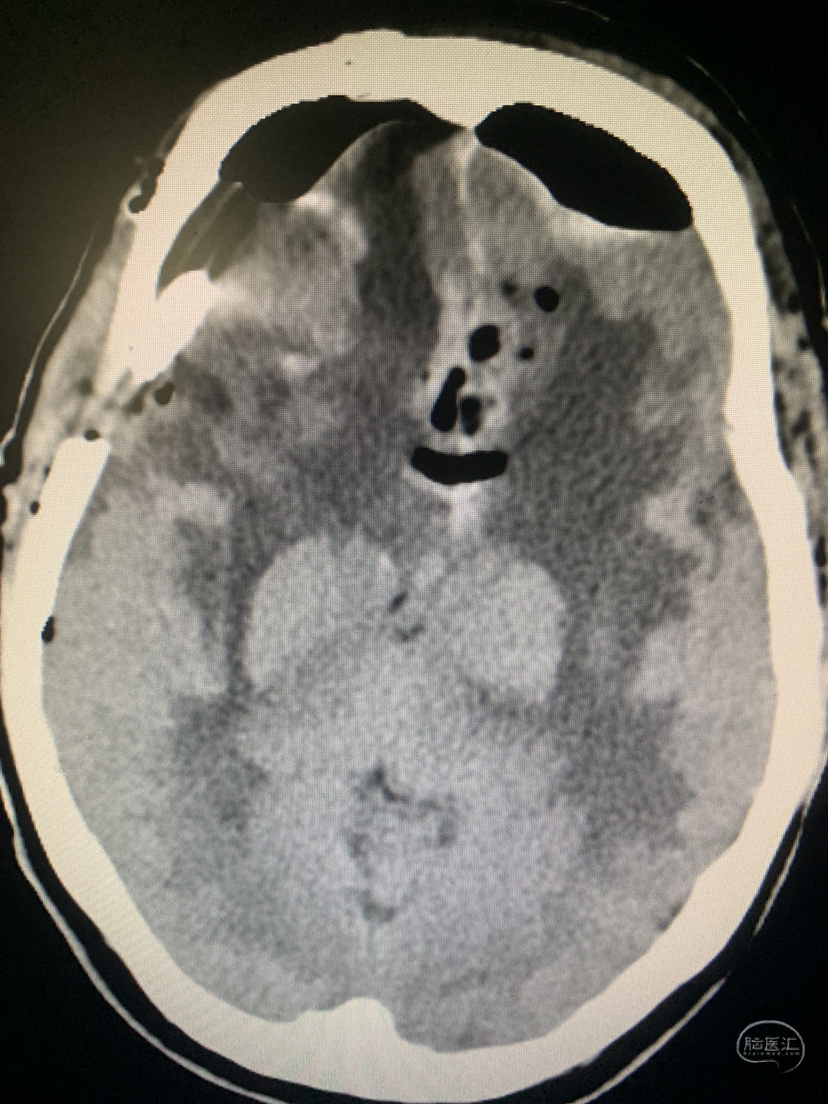

术前CT

术前CT